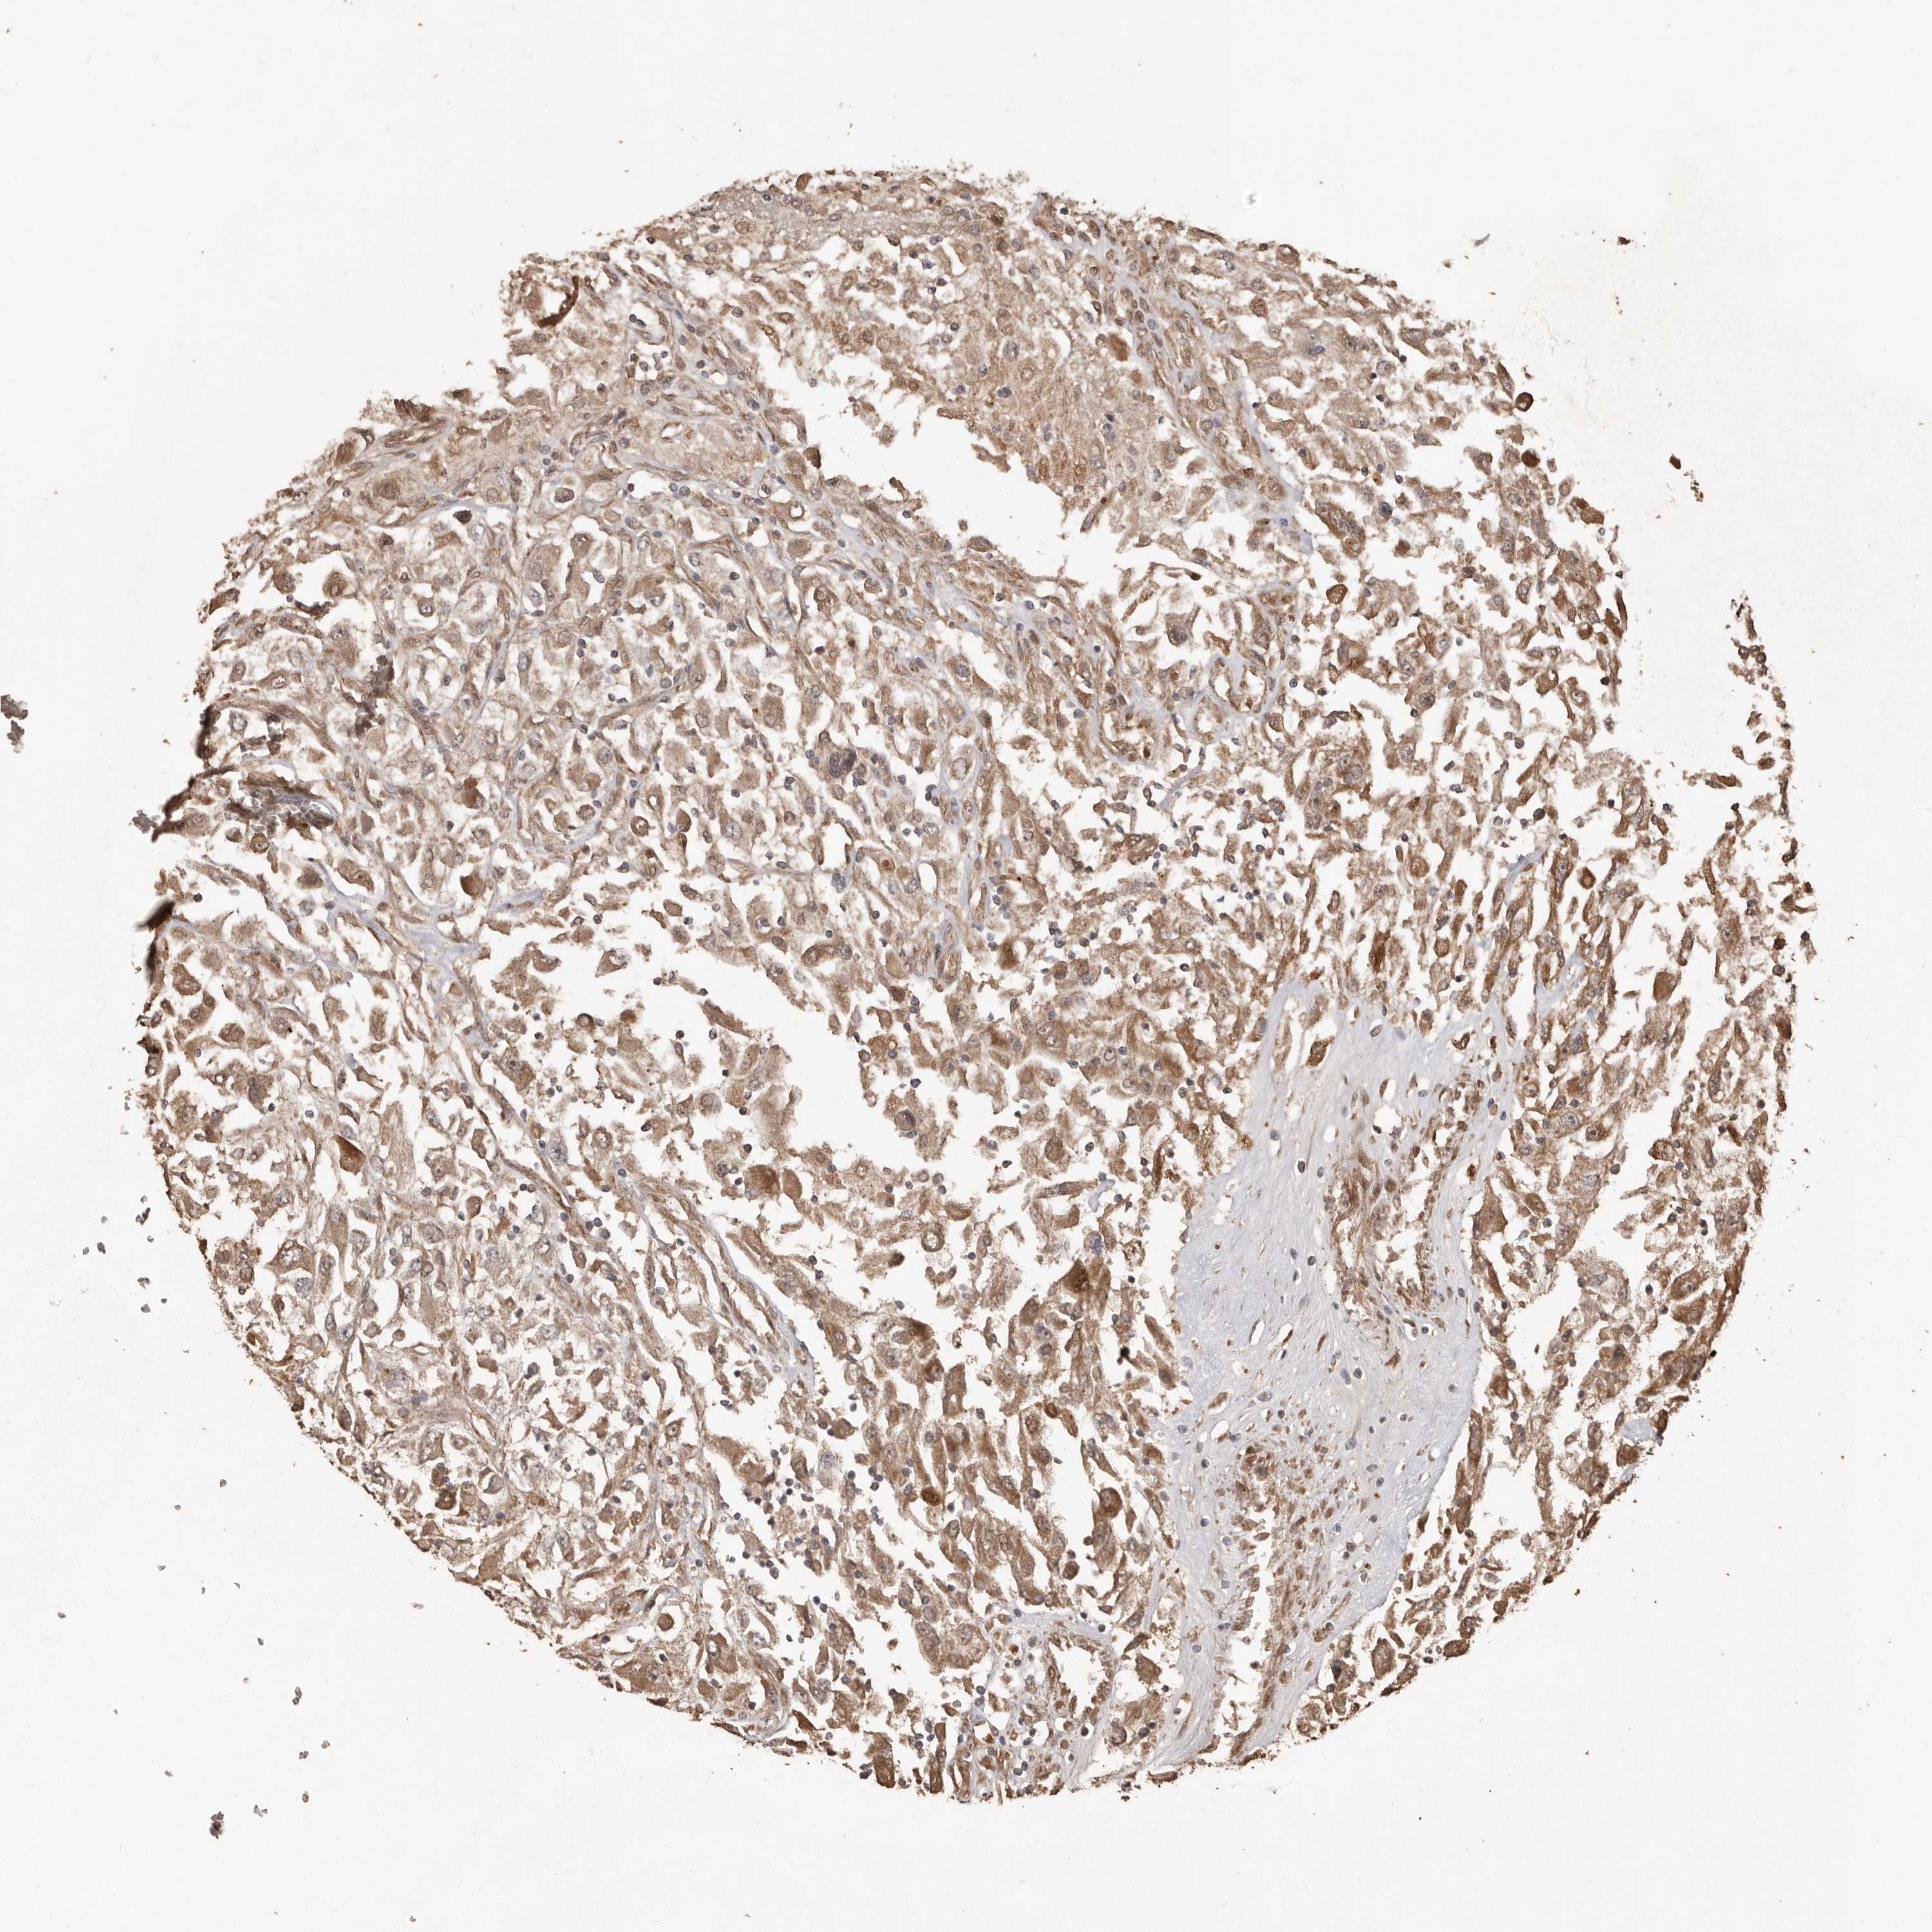

CANCER RENAL CANCER Show tissue menu

KICH TCGA KIRC TCGA KIRC VALIDATION KIRP TCGA PROTEIN RCC CPTAC PROTEIN EXPRESSION